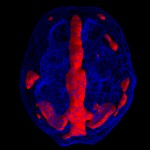

Možganska slika 68 letne ženske, ki so jo zdravili za Alzheimerjevo boleznijo. Predvidevali so da gre za ta tip demence zaradi simptomov, ki jih je imela – pogosto je pozabila imena svojih otrok, vnukov, se izgubila…Ampak možganska slika je pokazala normalno aktivnost v frontalnih in temporalnih predelih, kar ni značilno za Alzheimerjevo bolezen. Edina nepravilnost v možganih je bila prevelika možganska aktivnost v limbičnem sistemu, kar je značilnost ljudi, ki trpijo za depresijo. Šele tako je lahko dobila pravilna zdravila, ki so zmanjšala simptome njene bolezni.